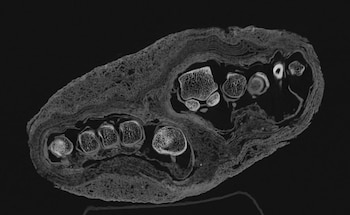

El uso del nuevo escáner ha permitido corregir errores de identificación en piezas que, durante décadas, habían sido mal catalogadas. Un caso paradigmático es el de un bulto momificado que fue considerado primero como una cabeza humana y luego como una posible momia de ave.

Solo las tomografías recientes comprobaron que se trataba de un pie adulto.

“A veces ni los expertos aciertan a la primera. Una muestra, antes atribuida a una cabeza humana o un pájaro, resultó ser el pie de un adulto”, reconoció la curadora principal Krisztina Scheffer.